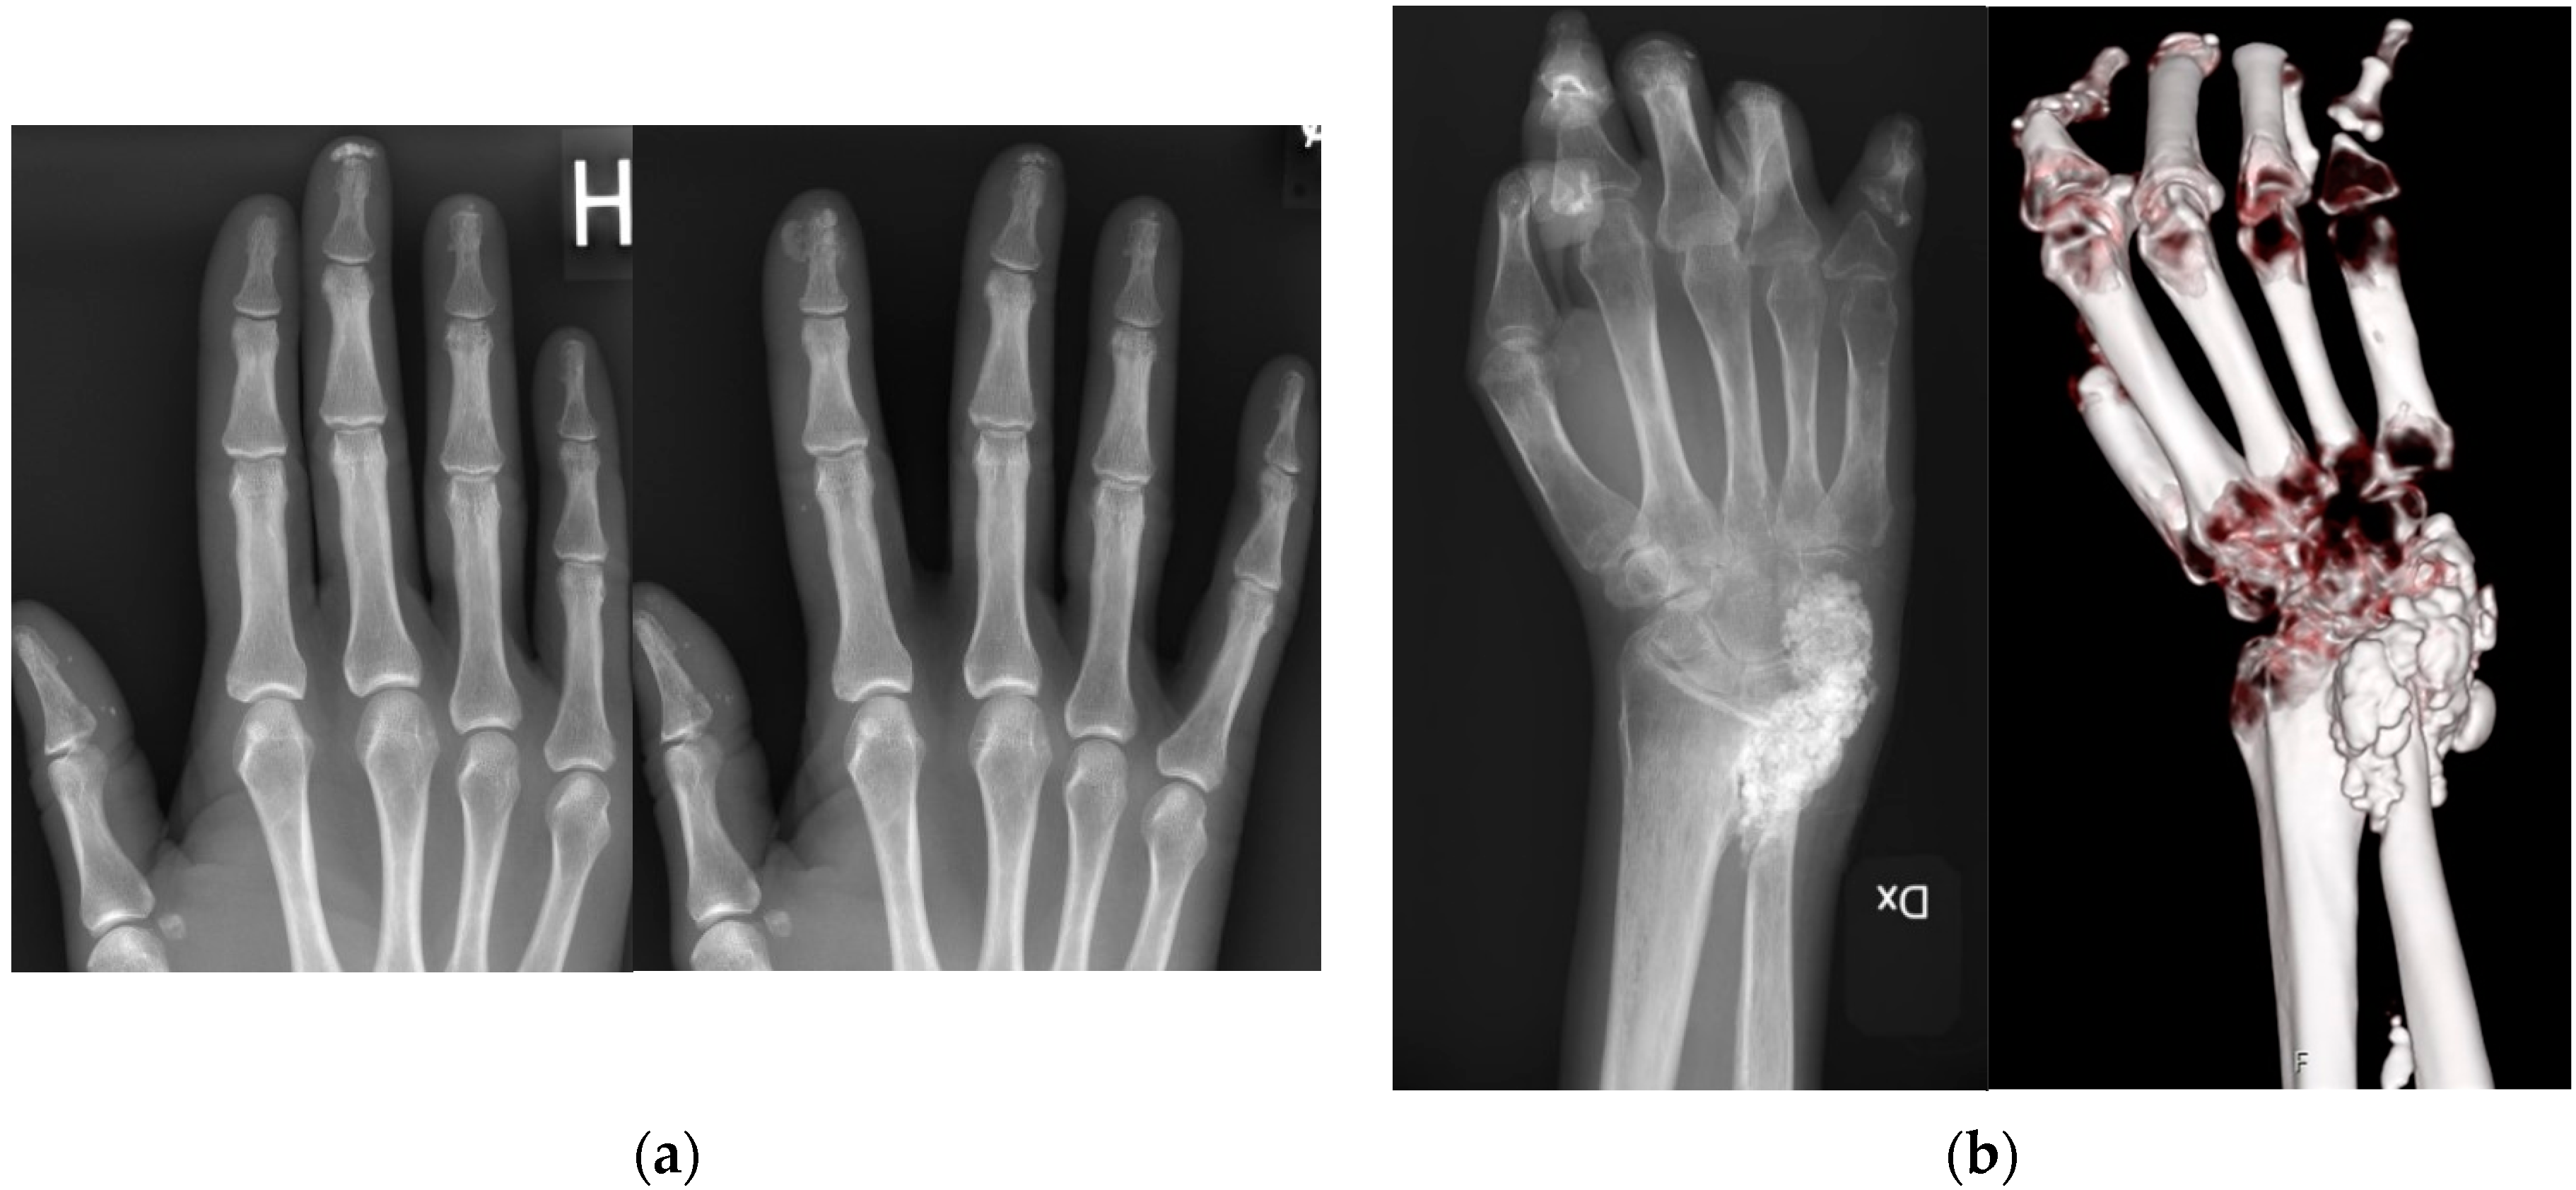

CC is diagnosed based on clinical examination supported by imaging techniques. While guidelines are sparse, the imaging gold standard is radiography, and other types of imaging such as ultrasound, computed tomography and magnetic resonance could provide extended information such as involvement of underlying structures. Larger studies comparing diagnostic accuracy are lacking. Diagnosis is occasionally confirmed through biopsy to identify calcium deposits in the skin or underlying tissues [27,28,29,30,31]. Figure 2. Calcinosis cutis imaging.

Figure 2.

(a) Radiographic and computed tomography (CT) image of the same hand and wrist in a 48-year-old female Ssc patient. Conventional radiography showing multilobulated calcifications in the distal radioulnar joint and ulnar side of the wrist, measuring 3 × 5 × 2 cm. To the right, a CT 3D multiplanar visualization with bone algorithm. (b) Radiographic image of the hand of a 65-year-old female SSc patient showing calcinosis observed in the distal parts of the first, third, and fourth fingers of the right hand. On the right side, a new radiography examination four years later shows new calcinosis formation at the distal part of the second finger, with some deposits measuring up to 4 mm. Furthermore, reduced density of calcinosis at the distal end of the third finger.